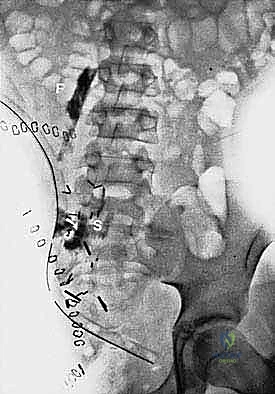

التصوير المقطعي المحوسب (CT Scan): يُستخدم لتقييم مدى تدمير العظام وتخطيط أماكن القص العظمي (Osteotomy) أثناء الجراحة.

-

الخزعة الطبية (Biopsy): يتم أخذ عينة من نسيج الورم بإبرة دقيقة تحت توجيه الأشعة، لتحليلها مخبرياً وتحديد نوع الخلايا السرطانية، وهو ما يحدد خطة العلاج (هل يحتاج المريض لعلاج كيماوي قبل الجراحة أم لا).